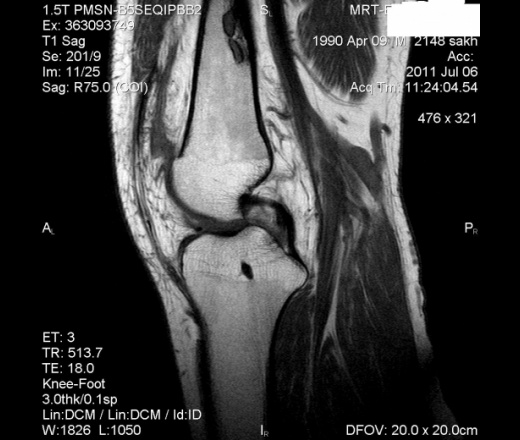

Трудно судить о состоянии суставов по столь скудному материалу, когда нет информативных срезов через связочный аппарат и мениски. Все что мне удалось разглядеть – это небольшой оссификат мыщелке правой бедренной кости, отек по наружному контуру латеральной головки икроножной мышцы (не исключена киста Бейкера), «прослойка» жидкости в супрапаттелярной сумки, незначительный боковой пролапс тела наружного мениска. Говорит о том, что творится в дистальном отделе метафиза бедренной кости (которую не потрудились прицельно порезать) – это гадание кофейной гуще. Рекомендуйте КТ либо доделывайте исследование.

А где надколенник?.................

энхондрома ? и правда где же надколенник ?

Действительно, а где надколенник?Надо поискать исследование в архиве.

может травма была и он был удален...

Нашла!Ура!Латерализация.